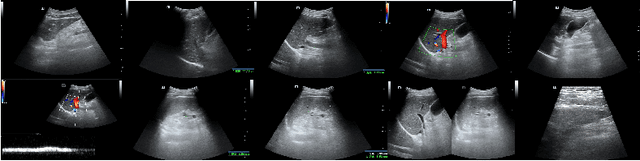

Abstract:Accurate analysis of the fibrosis stage plays very important roles in follow-up of patients with chronic hepatitis B infection. In this paper, a deep learning framework is presented for automatically liver fibrosis prediction. On contrary of previous works, our approach can take use of the information provided by multiple ultrasound images. An indicator-guided learning mechanism is further proposed to ease the training of the proposed model. This follows the workflow of clinical diagnosis and make the prediction procedure interpretable. To support the training, a dataset is well-collected which contains the ultrasound videos/images, indicators and labels of 229 patients. As demonstrated in the experimental results, our proposed model shows its effectiveness by achieving the state-of-the-art performance, specifically, the accuracy is 65.6%(20% higher than previous best).